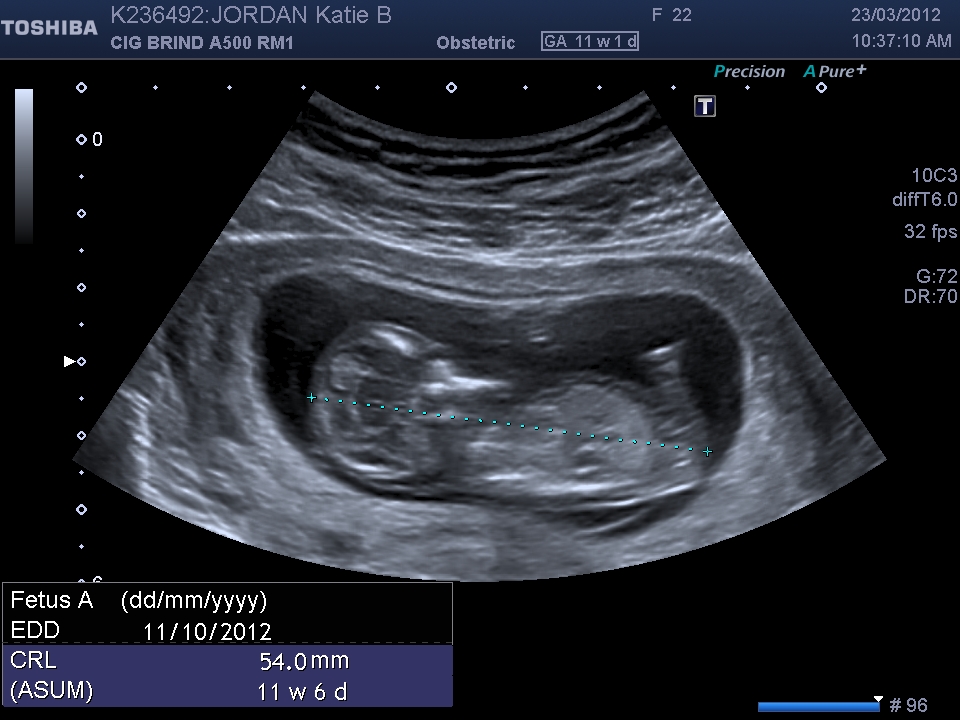

11w 1d is a bit early.

had my gender scan today def a lil boy yay im so happy

Congrats! Enjoy your little boy. Xx